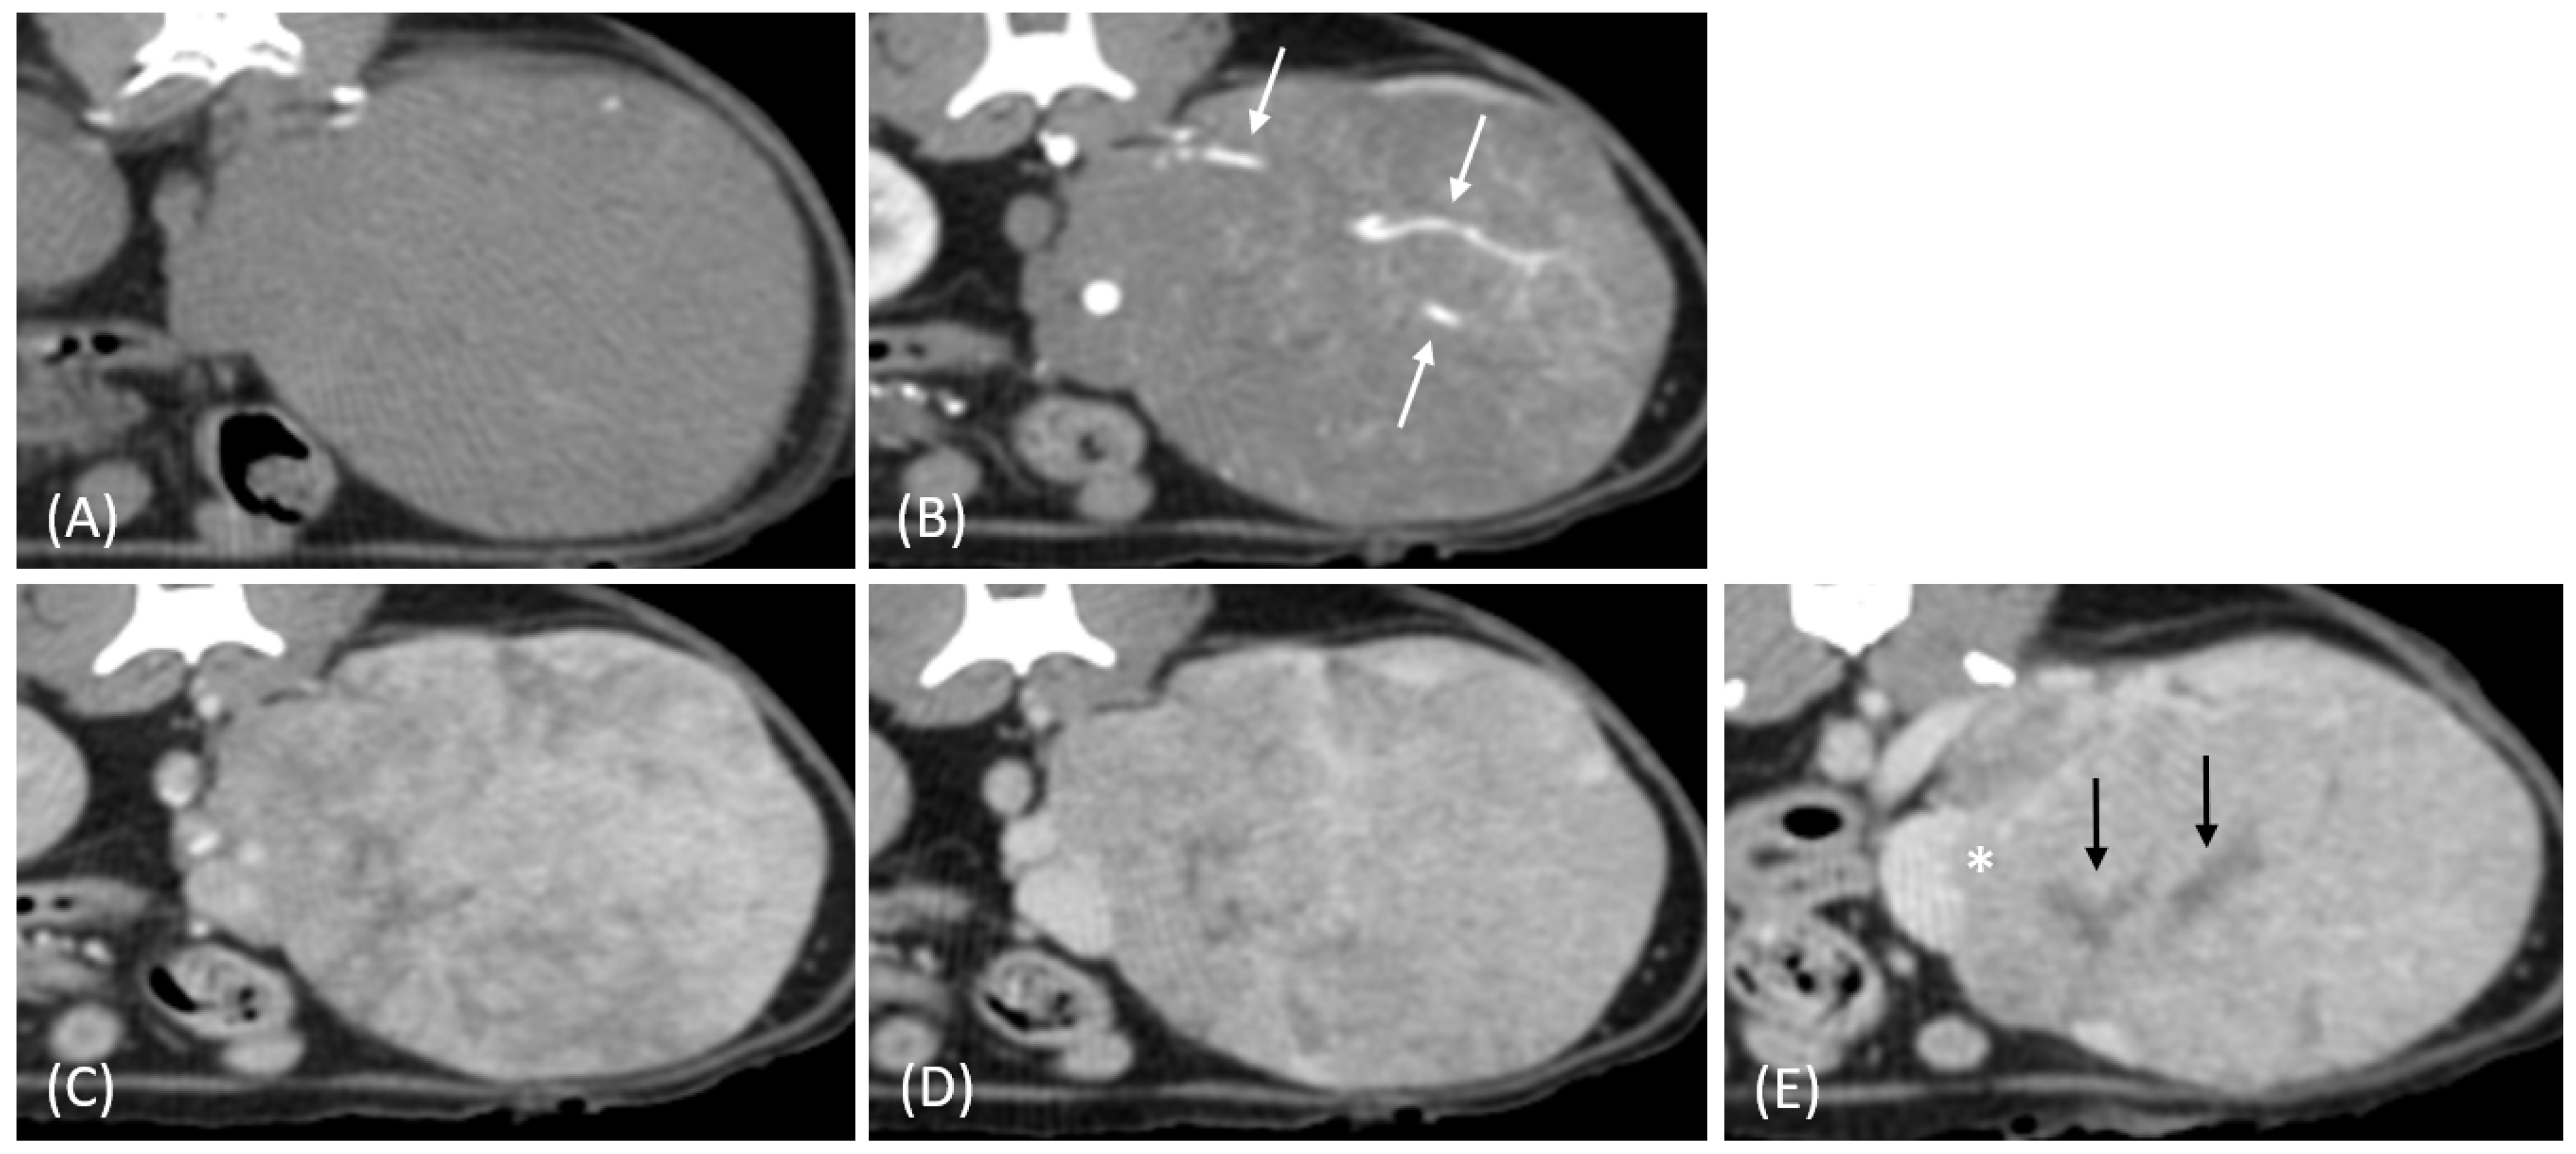

Figure 1.

(A) Pre-contrast, (B) corticomedullary phase, (C) nephrographic phase, and (D,E) late nephrographic/early excretory phase contrast-enhanced computed tomography (CT) images of a cat with a unilateral left renal cell carcinoma. The mass is heterogeneous, with tumor vessel enhancement (white arrow) noted in the corticomedullary phase. Progressive enhancement is observed, along with internal necrosis (black arrow). The renal vein is enlarged with tumor invasion (asterisk), but no invasion into the caudal vena cava (CVC) is seen. The tumor encases the renal artery, though definitive arterial invasion is not apparent.